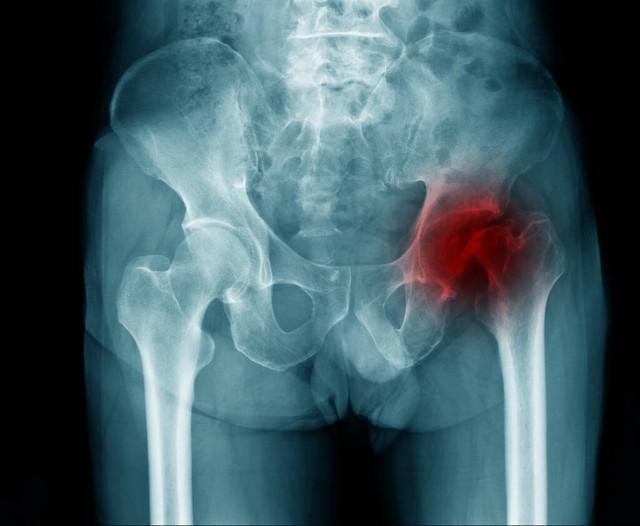

骨頭壞死是指骨組織因各種原因?qū)е卵汗?yīng)不足,從而使骨細(xì)胞死亡和骨組織破壞的過(guò)程,骨頭壞死的原因包括創(chuàng)傷、感染、長(zhǎng)期應(yīng)用激素、骨質(zhì)疏松等,骨頭壞死后,患者可能出現(xiàn)疼痛、腫脹、活動(dòng)受限等癥狀。

骨頭壞死后能否恢復(fù)取決于病情的嚴(yán)重程度、發(fā)現(xiàn)時(shí)機(jī)及治療方法,在骨頭壞死的早期階段,通過(guò)適當(dāng)?shù)闹委熀涂祻?fù)措施,有可能實(shí)現(xiàn)骨組織的再生和恢復(fù),如果病情嚴(yán)重或治療不及時(shí),可能會(huì)導(dǎo)致骨組織的不可逆損害,影響恢復(fù)。